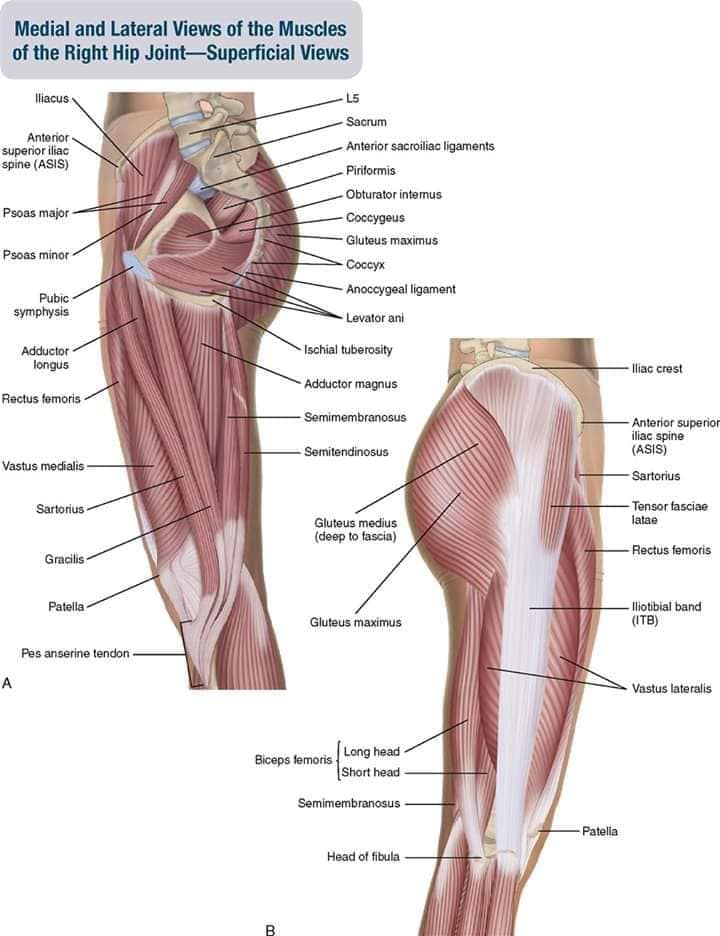

Скелетно-м'язова система людини (синоніми: Опорно-рухова система, опорно-руховий апарат, кістково-м'язова система, локомоторна система) — комплекс структур який утворює каркас, надає форму організму, дає йому опору та забезпечує захист внутрішніх органів і можливість пересування у просторі. Це функціональна сукупність кісток скелета, їх з'єднань (суглобів і сінартрозів), і соматичної мускулатури з допоміжними пристосуваннями, які здійснюють за допомогою нервової регуляції локомоції, підтримання пози, міміки та інших рухових діях, поряд з іншими системами органів утворює людське тіло.

Це саморушний механізм, який складається з 400 м'язів, 206 кісток і декількох сотень сухожиль. Більшість кісток скелету з'єднане рухомо за допомогою суглобів. Одним кінцем м'яз прикріплюється до однієї кістки, утворюючи суглоб, іншим кінцем — до іншої кістки. В англомовній літературі застосовують близькі за значенням терміни: англ. musculoskeletal system (скелетно-м'язова система) та англ. locomotor system (локомоторна система).

М'язова система людини є однією з основних систем організму, що відповідає за рухи, підтримання пози та стабільність. Вона складається з понад 600 м'язів, які можна класифікувати на скелетні, гладкі та серцеві м'язи. Скелетні м'язи, які є об'єктом нашого детального розгляду, дозволяють контролювати навколишній світ і виконувати різноманітні рухи. Особливу увагу в нашій статті буде приділено шейним і спинним м'язам, оскільки ці групи м'язів мають критичне значення для підтримання правильного постава та функціонування хребта.